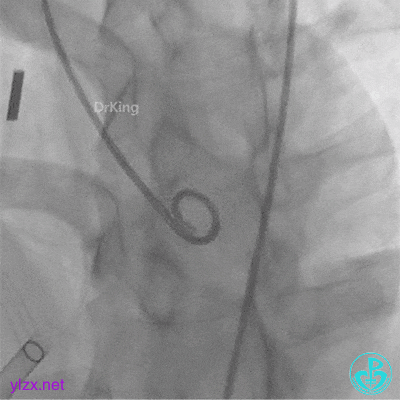

封堵器完全释放后位置、形态观察

封堵器完全释放后盘面平整,呈“工”字型骑跨于室间隔两侧,未见瓣膜影响。